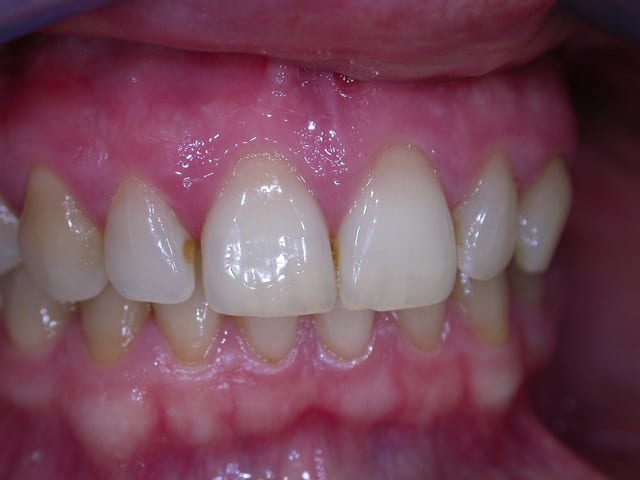

examen buccal .........voir les photos ........après ........ca vient

examen radio .........après ca vient.......

Bon controle de plaque, pas de tartre ni de colorations, inflammation en palatin seulement...